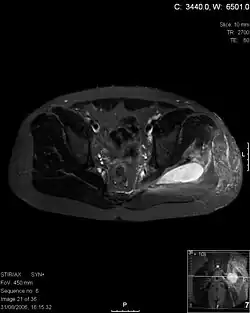

Die wichtigsten Diagnosemethoden beim Verdacht auf Pyomyositis sind bildgebende Verfahren wie die Sonographie, mit welcher Störungen der Muskelstruktur sowie das Vorhandensein von Eiteransammlungen in der Muskulatur bestätigt werden können. Der Nutzen ist jedoch eingeschränkt während der ersten Phase der Erkrankung. Mit einer Computertomographie können vor dem Auftreten von Abszessen Muskelschwellungen und verringerte Muskeldichte nachgewiesen werden, mit einer MRT-Untersuchung lassen sich Ausmaß und Lokalisation der Erkrankung beurteilen. Als Referenzmethode zum Nachweis multipler Abszesse gilt eine Gallium-Szintigraphie. Bildgebende Verfahren sind darüber hinaus wichtig für die Verlaufskontrolle.

- Pyomyositis: MRI images MRI-Bilder von Pyomyositis-Infektionen (englisch)